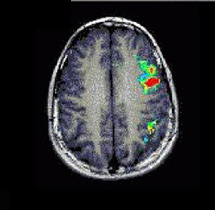

Caso 1

Paciente Paciente de sexo femenino de 19 años de edad.   Demostración prequirúrgica de áreas elocuentes

Paradigma Fluidez fonética

ACTIVADO: Generación en silencio de palabras que comienzan con una letra dada

DESACTIVADO: No pensar en nada

Resultados Activación de las circunvoluciones frontales izquierdas medias e inferiores, corteza izquierda precentral, circunvoluciones angulares izquierdas y áreas dispersas en los lóbulos parietales.

Comentarios El área principal activada en esta tarea de fluidez fonética es la cara superior de la circunvolución frontal inferior izquierda.   En cambio, el área principal de activación en las tareas que requieren generación de verbos es la cara inferior del área de Broca, junto con la ínsula anterior.